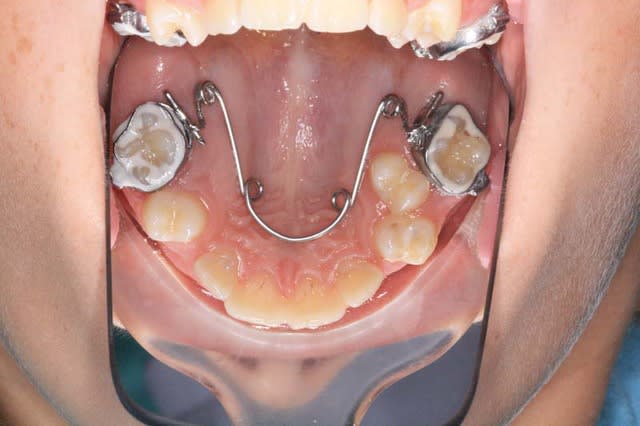

Voici, par exemple, un cas en fin de TTT.

+ Bjc.

Img 1 qmasah - Eugenol

Img 2 vtedrr - Eugenol

Img 3 zxbzaf - Eugenol